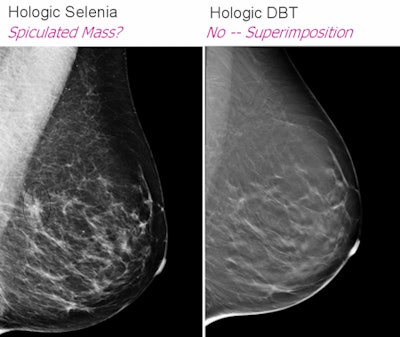

With its 3D lesion localization capability, digital breast tomosynthesis (DBT) can get around mammography's overlapping tissue problem, Rush said. Hologic (Bedford, MA), GE Healthcare (Chalfont St. Giles, U.K.), and Siemens Healthcare (Malvern, PA) all have work-in-progress units, and Hologic has submitted a premarket approval application to the U.S. Food and Drug Administration.

With a DBT unit, both DBT and full-field digital mammography (FFDM) exams will be performed under a single compression, in craniocaudal and mediolateral oblique views. And although the radiation dose will not decrease, the exam will still require less radiation than is allowed in FFDM.

![]() |

| Slide courtesy of Bonnie Rush (images from Hologic). |

"FFDM plus DBT makes it easier to find changes in the breast than just FFDM alone," Rush said. "The combination has the potential to reduce screening recall rates by up to 40%. This will open up schedules and cut down on patient anxiety."